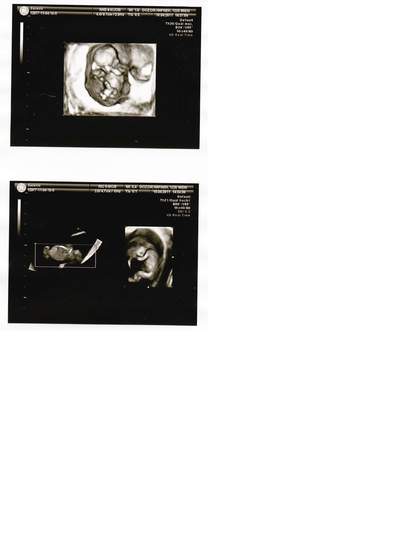

Jestem juz po wizytce i dziekuje za Wasze kciuki-> przydaly sie. Maluszki kompletnie zdrowe, oboje identycznej wielkosci, 4,85 cm, przeziernosc karkowa idealna. I co najwazniejsze, wedle mego lekarza, ktory zrobil obraz 3d na 80-90% bedzie chlopczyk i dziewczynka. Jestem przeszczesliwa.

11t3d_a.jpg11t3d.jpg